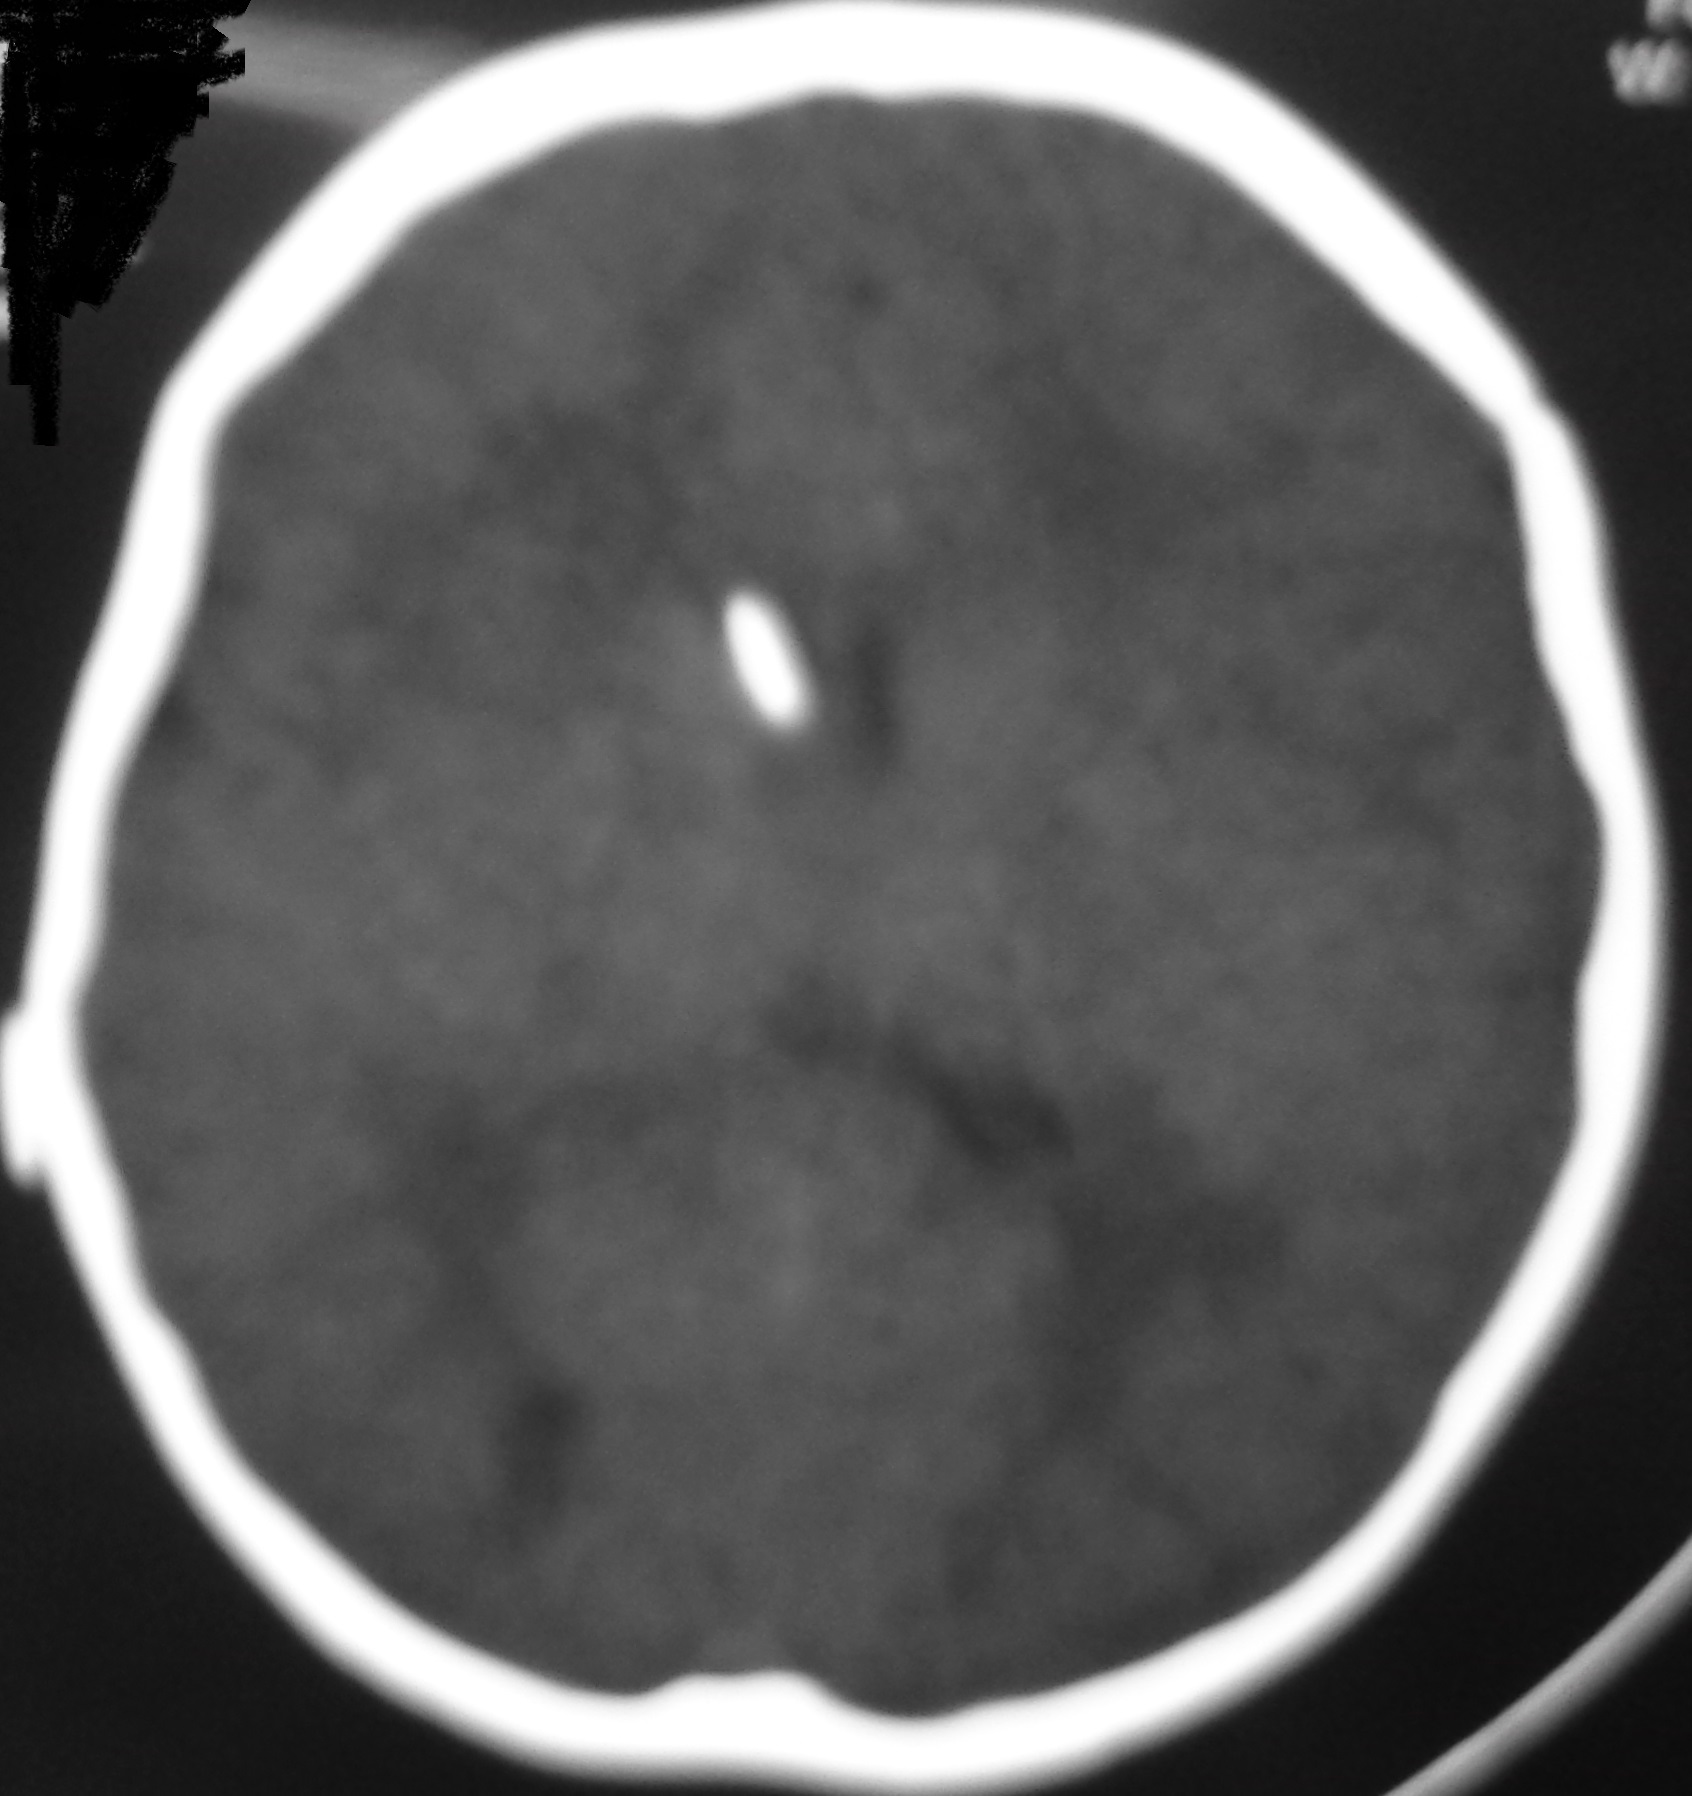

The signs and symptoms of shunt dysfunction are related to high intracranial pressure most commonly including headache, nausea, vomiting, bulge fontanel, irritability, sunset eye. Increased ventricular diameter in comparison to prior studies, increased temporal horns width, sulcus effacement and rounding of 3rd ventricle are common findings in neuroimaging studies during shunt malfunction (Figure 1). However, stable ventricular dimensions on serial imaging studies (Figure 2) may wrongly be interpreted as normal shunt function [4].

Figure 2: A. Slit like ventricle after 9 months of shunting in an infant with congenital hydrocephalus; the child was stable without any symptoms. B. One year later he was admitted with persistent vomiting and ptosis. The brain CT shows no obvious change in the size of ventricle. His symptoms were recovered after shunt revision due to proximal catheter obstruction.